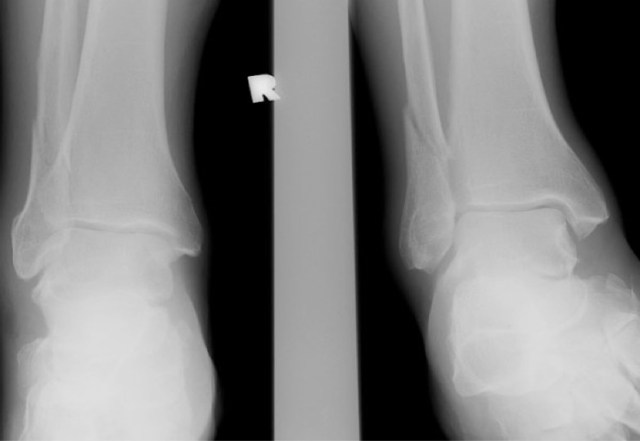

Frontal and mortise radiographs of right ankle. Essentially non-displaced right suprasyndesmotic distal fibular shaft fracture. No overt lateral or medial ankle joint space widening.